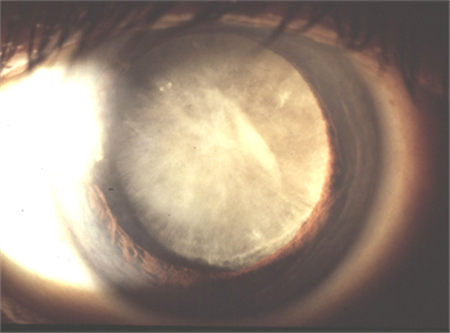

正常情況下,我們眼內的晶狀體呈透明狀態(tài),能夠將光線準確聚焦于視網(wǎng)膜上,是重要的屈光介質。由于年齡增長、眼外傷、免疫與代謝異常、中毒等原因,導致晶狀體發(fā)生變性而變得不再透明,也就形成了白內障。

就像模糊的鏡頭無法拍攝出清晰的照片,白內障患者由于晶狀體混濁,視力也會受到不同程度的影響,隨著病情發(fā)展,晶狀體變得完全混濁,可直接導致失明。相機的鏡頭修不好可以重新?lián)Q一個,白內障也是一樣,已經(jīng)發(fā)生變性的晶狀體無法恢復原狀,但我們可以直接給眼睛更換一個人工晶體。